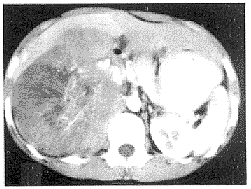

副神經節起源的腫瘤CT圖非嗜鉻性副節瘤(“副節瘤”、“化感瘤”)此瘤比較少見。張遜等(1994)報導,在同期縱隔腫瘤的0.52%~4.3%;張合林(1995)年報導占10.74%,這可能與醫院收治的範圍有關。可見於中縱隔及後縱隔的脊柱旁溝,後者更常見。多數為良性只有10%左右為惡性。副節瘤大多為“非功能性”但偶爾可有功能活性。神經分泌產物主要為去甲腎上腺素。亦可有微量腎上腺素臨床上可出現嗜鉻細胞瘤的典型症狀,按摩腫瘤可使血壓升高。非功能性副節瘤用電鏡細胞化學方法可顯示神經分泌顆粒生化測定可精確定量去甲腎上腺素及腎上腺素的含量(可高達24.5μg/g瘤組織)。當含量達1.5mg/g時可出現典型的嗜鉻細胞瘤症狀。

2.CT掃描顯示 前縱隔主動脈弓旁或後縱隔腫物多為實質性的,密度均勻的陰影,有時可見條索狀密影與主動脈相連。由於這種腫瘤血管豐富,CT增強掃描腫瘤可明顯強化顯影。